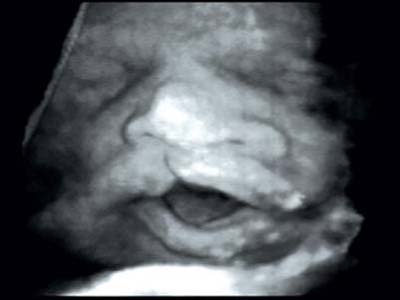

Atteinte associée du palais